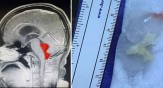

വര്ഷങ്ങള് നീണ്ട കടുത്ത തലവേദനയും ഛര്ദിയും; തലച്ചോര് സ്കാന് ചെയ്തപ്പോള്...

ടെക്സാസ് സ്വദേശിയായ ജെറാര്ഡോ കഴിഞ്ഞ കുറേ വര്ഷങ്ങളായി കടുത്ത തലവേദനയുമായാണ് കഴിഞ്ഞിരുന്നത്. മൈഗ്രേയ്ന് ആയിരിക്കാം എന്നായിരുന്നു കരുതിയിരുന്നത്. അതിനാല് വേദനയ്ക്കുള്ള മരുന്ന് കഴിച്ച് വിശ്രമം എടുക്കു...